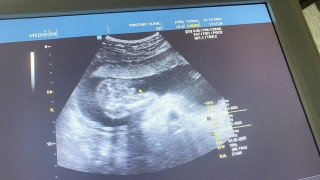

ฝังมา 10 ปี ไม่ได้เอาออก ตอนนี้ตรวจขึ้น2ขีด ค่ะ🥰

ตอนนี้ทะลุเรียบร้อยฝัง 4ปี2เดือน